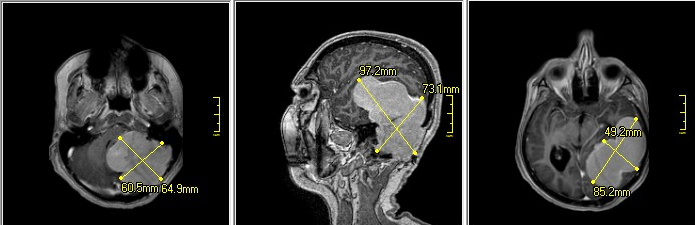

"Невероятно, но больная в течение следующих 22 лет никуда не обращалась и не наблюдалась неврологами, пока не появились жалобы, похожие на те, что были в далеком 1998 году. В приемное отделение больную доставили ургентно, самостоятельно она не передвигалась. Выполнено МРТ головного мозга, результаты исследования шокировали, как врача МРТ, так и нейрохирургов. Опухоль приобрела огромные размеры - более 10 см. Это, пожалуй, самая огромная опухоль за весь период существования нейрохирургической службы в нашем регионе", - написал Александр Марченко.